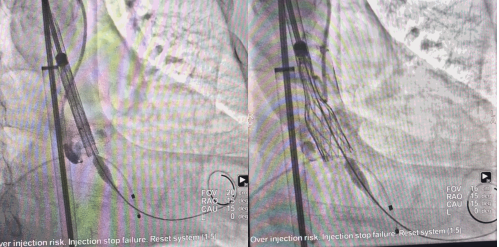

预扩完成后可进行瓣膜输送及释放,预期植入位置为自身主动脉瓣环平面。采用分阶段释放方式,预先释放使得瓣膜底端露出,便于精准定位;之后释放至人工瓣工作位,可以整体评估瓣膜的位置和功能,评估完成后进行第三阶段完全释放;若评估位置不合适,也可以进行回收再次定位释放。

经工作位(右图)评估,人工瓣底端位于目标位置,瓣架锚定牢固,符合释放条件,可以完全释放。术后造影显示人工瓣膜位置良好,功能正常,未见瓣周漏,左心室-主动脉压差降至10mmHg以下,手术取得圆满成功。